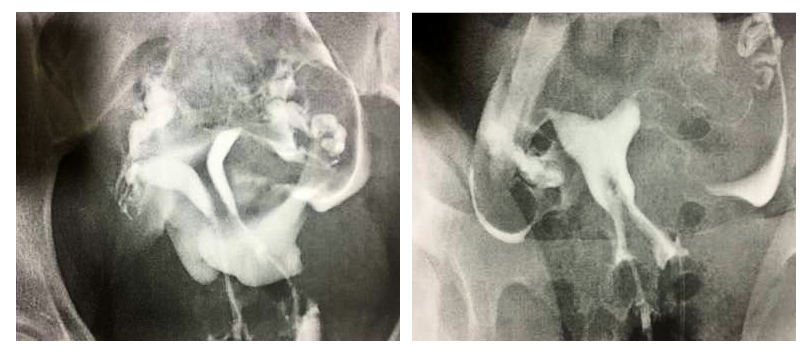

The patient you see below is a 25-year-old woman who presented with a desire to become pregnant. The images below show her pre- and post-operative hysterosalpingograms. The uterine septum was completely removed in surgery.